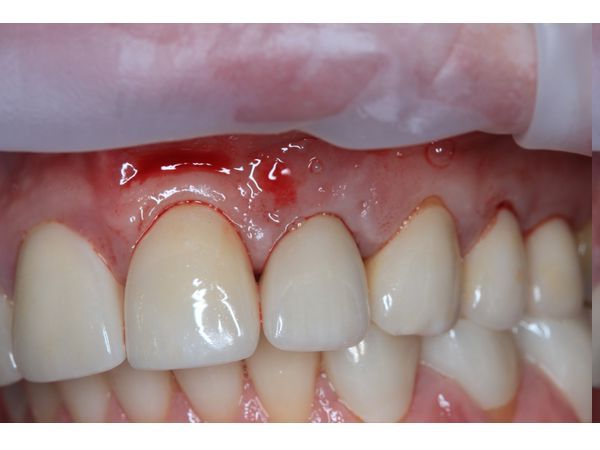

При осмотре отмечалась подвижность коронковой части зуба. На внешней стороне десны определялось отверстие, из которого при надавливании сочилась кровь.